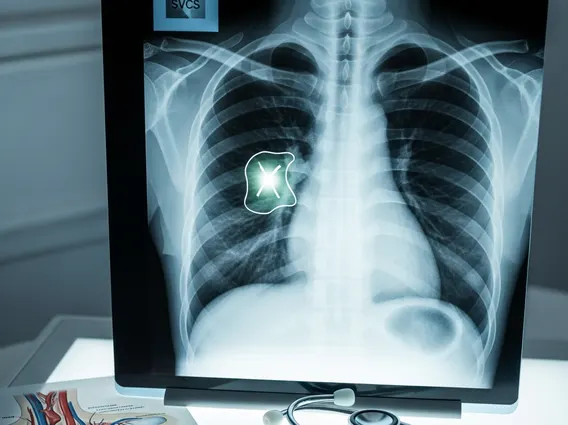

Superior Vena Cava Syndrome

Superior Vena Cava Syndrome is a serious medical condition resulting from obstruction of the superior vena cava, a major vein that carries blood from the upper body to the heart. This obstruction can lead to a range of symptoms primarily affecting the head, neck, and upper extremities.

Superior Vena Cava Syndrome (SVCS) refers to a collection of signs and symptoms caused by the obstruction of blood flow through the superior vena cava (SVC). The SVC is a large vein responsible for draining deoxygenated blood from the head, neck, upper chest, and arms into the right atrium of the heart. When this vein becomes compressed or blocked, blood flow is impaired, leading to increased venous pressure in the areas it drains.

This obstruction can result from external compression, such as by a tumor, or from an internal blockage, like a blood clot. The severity of the syndrome depends on the degree of obstruction, the rate at which it develops, and the effectiveness of collateral circulation (alternative blood flow pathways) that may develop to bypass the blockage. Understanding the nature of this obstruction is key to effective management and treatment.